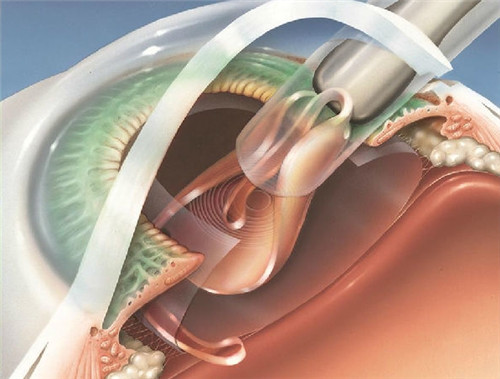

家人们,我做白内障三焦晶体植入手术已经有一段时间啦,现在来给大家好好分享下我1个月和6个月的真实感受,真的就像告别了“毛玻璃”国内外,重见清晰光明!

三焦切换超流畅,就跟变魔术似的,想看哪儿,眼睛立马就能适应。

而且啊,这眼睛就跟上了润滑油的机器一样,不管是看远、看中还是看近,都能快速调整到理想状态,一点儿都不费劲。

我都忍不住感叹,这三焦晶体植入手术简直就是我的救星,让我重新找回了清晰的视野。